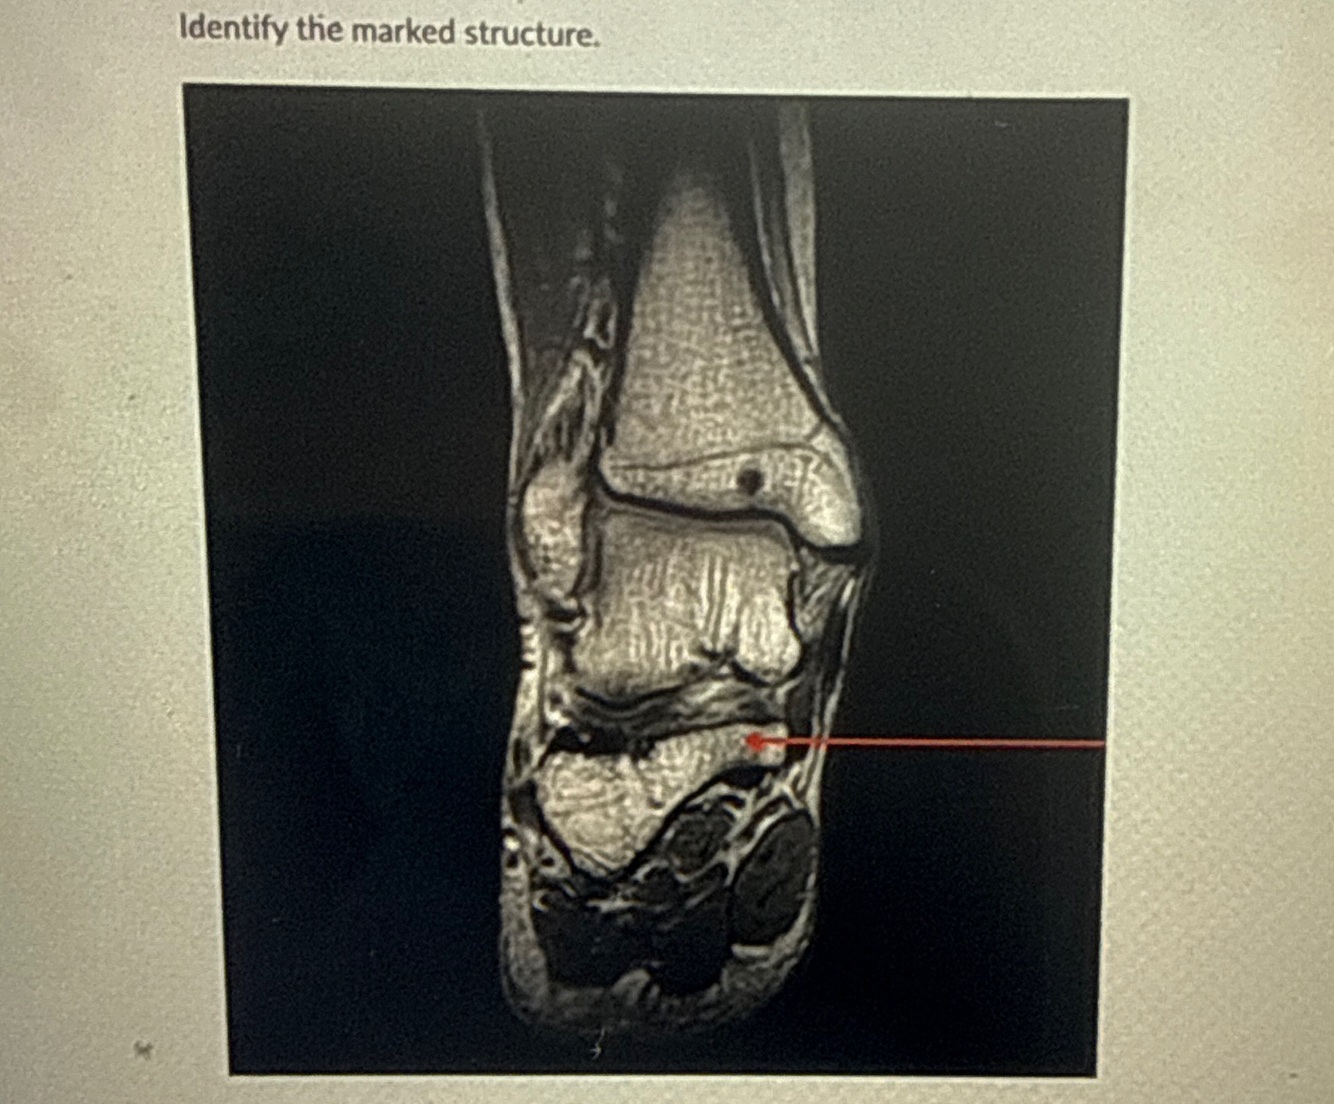

3

Q

Arrow points to

A

Deltoid ligment